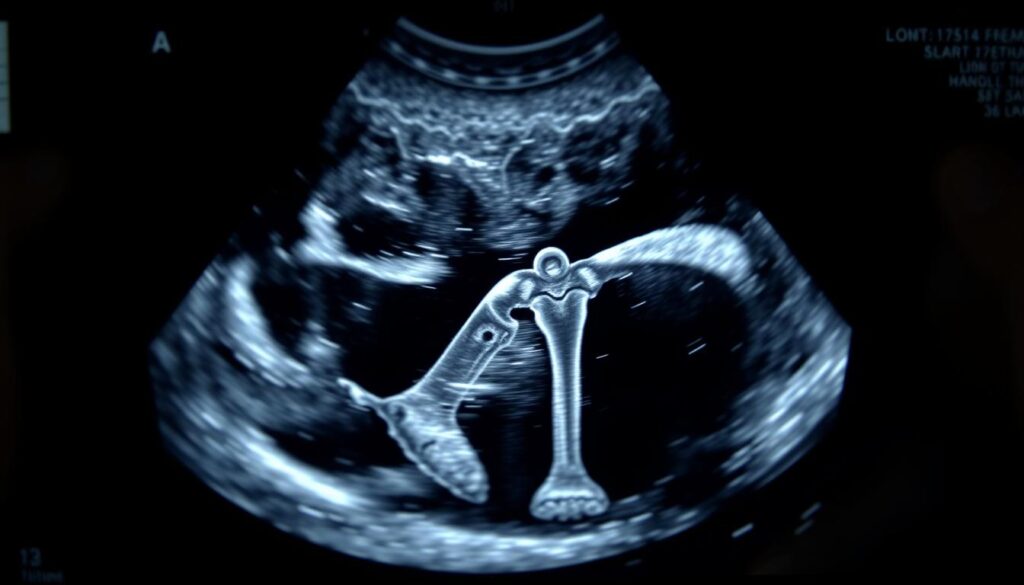

Hallo, ich bin Maja vom mama-hilft.de-Team. Wussten Sie, dass der Oberschenkelknochen Ihres ungeborenen Babys einer der wichtigsten Hinweise auf seine gesunde Entwicklung ist? Bei fast jeder Ultraschall-Untersuchung wird diese Länge genau vermessen.

Diese Messung, die Femurlänge, gibt Ärzten 2025 wertvolle Informationen über die Größe und den Entwicklungsstand Ihres Babys. Sie hilft, das ungefähre Gewicht und den Wachstumsfortschritt zu bestimmen.

Was genau verbirgt sich hinter dem medizinischen Begriff Femur, den Sie in Ihrem Mutterpass finden? Dieser Fachausdruck bezeichnet den Oberschenkelknochen. Es handelt sich um den längsten Röhrenknochen im menschlichen Körper.

Die Länge dieses Knochens bei Ihrem Baby gibt wertvolle Hinweise auf seine Entwicklung. Da eine direkte Messung der Körpergröße im Mutterleib oft schwierig ist, dient die Femurlänge als guter Indikator.

Ab der 12. Schwangerschaftswoche ist das Ungeborene groß genug für zuverlässige Messungen. Der Knochen ist dann im Ultraschall gut sichtbar. Daher beginnt die routinemäßige Kontrolle der Femurlänge zu diesem Zeitpunkt.

Die Ärztin misst die Länge des Oberschenkelknochens von einem Ende zum anderen. Diese Methode ist sicher und nicht-invasiv. Sie gehört im Jahr 2025 zum Standard der Vorsorge.